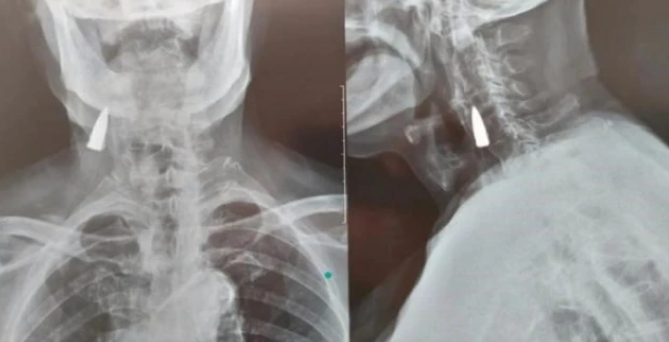

据回忆大概是抗日战争时期

背着受伤的战友过河时受的伤

岳父之前并没有感觉到头部有什么不适

身体也不错

“以前他也没注意到这个地方

发现了以后就挺震惊的”